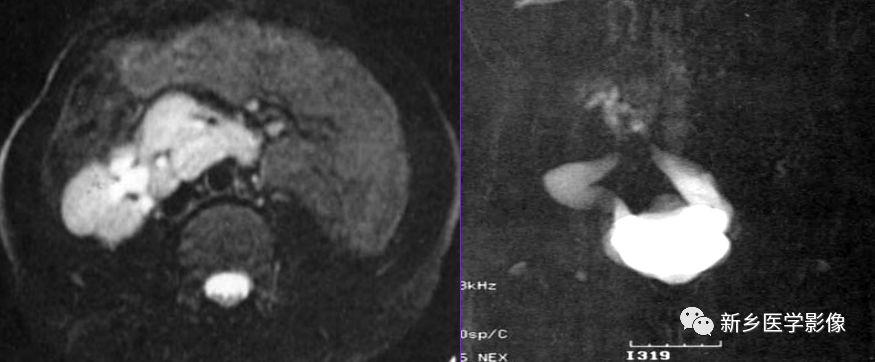

MR特点

双肾下极越过中线,以实质或纤维性连接。合并结石、积水可见不规则T1WI低、T2WI低或高信号,边缘清晰及扩大的肾盂。合并肿瘤可见不规则的T1WI低、T2WI低、高信号,合并出血或坏死可出现 明显T1WI低、T2WI低信号或高信号。冠状面可见拉长的下肾盏结构,可见到起源于主动脉较低水平的多支供血动脉及其他畸形。

马蹄肾是最常见的融合肾类型,不合并肾肿瘤或炎症等病变时,临床无症状。CT和MR可明确诊断。但需注意并发症的存在及血供情况。